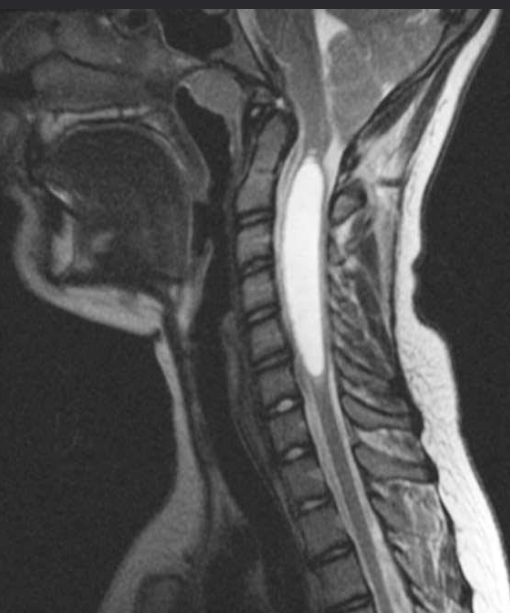

Cervical disk herniation

MRI cervical spine (T2-weighted; sagittal plane) of a

patient with symptoms of cervical myelopathy

A herniated disk at C5–6 effaces the dural sac and compresses the spinal cord. Hyperintense compression-induced edema is seen within the cord